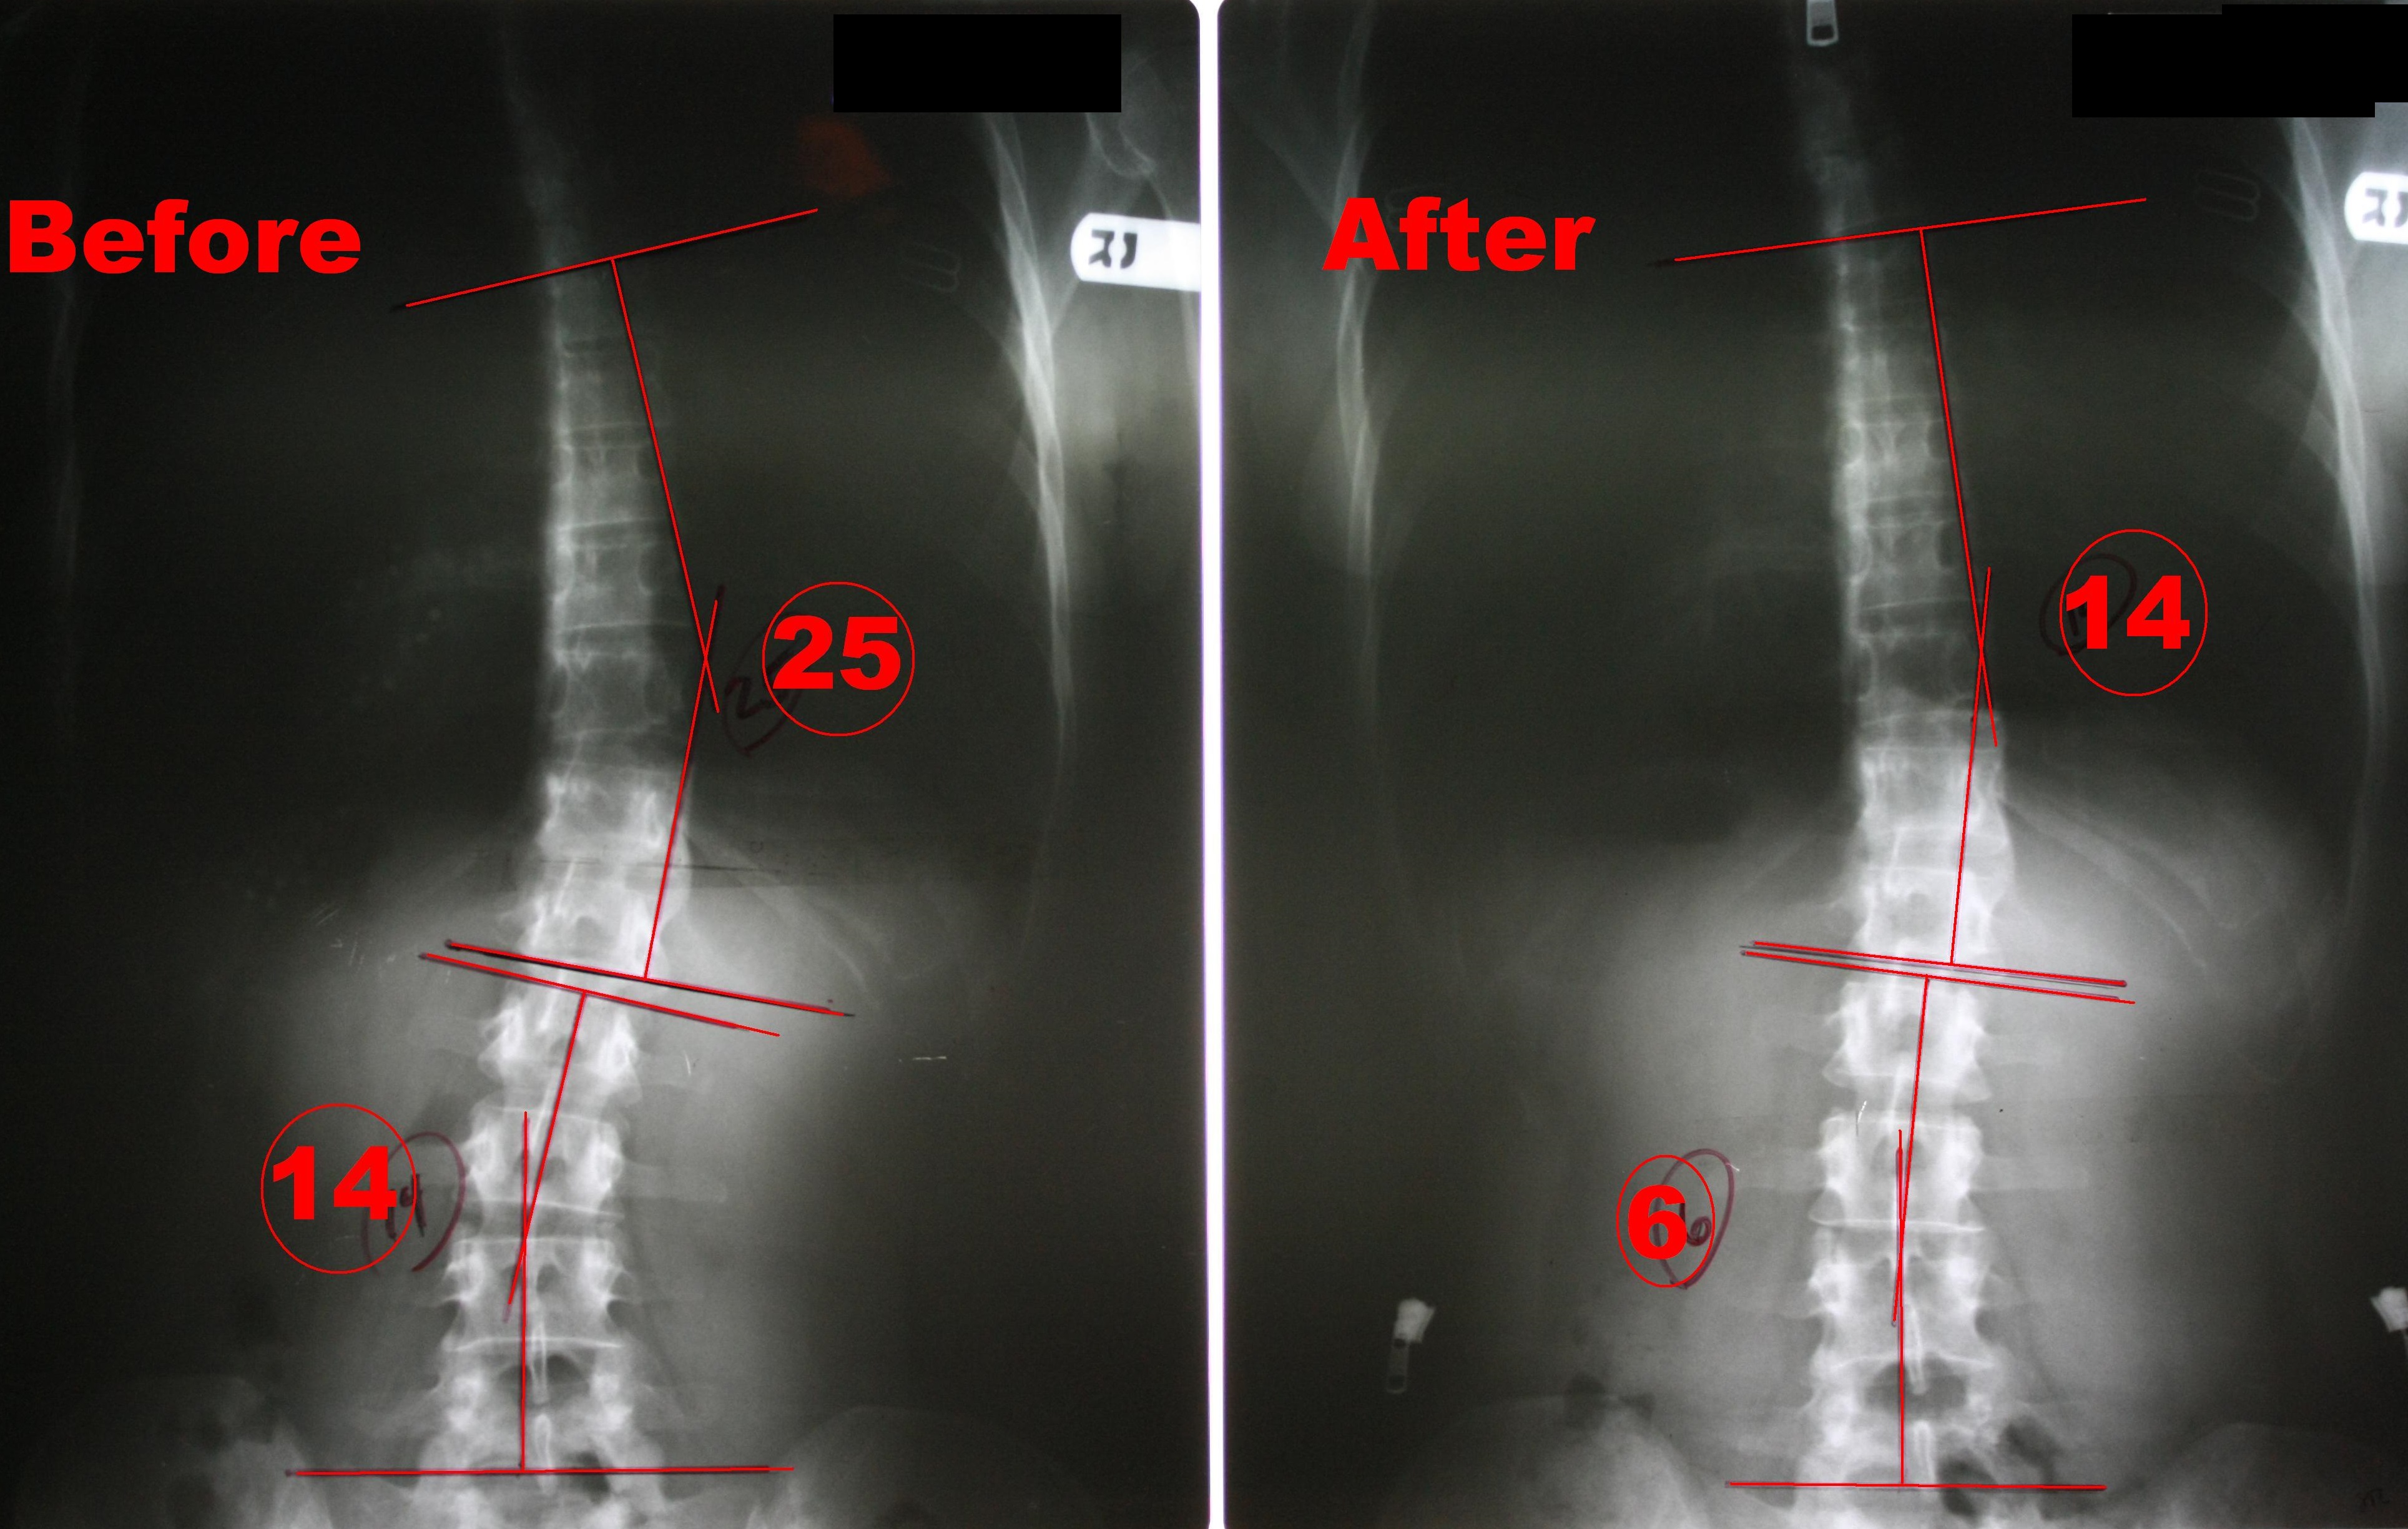

Scoliosis Surgery Before and After Scoliosis Institute Everyone has normal curves in the spine, and when looked at from behind, the spine appears straight. for chiropractors who find themselves called to serve the scoliosis population, clear scoliosis certification provides a. Scoliosis is a sideways curve of the spine. scoliosis is a sideways curvature of the spine that most often is diagnosed in adolescents. when. Scoliosis Institute.